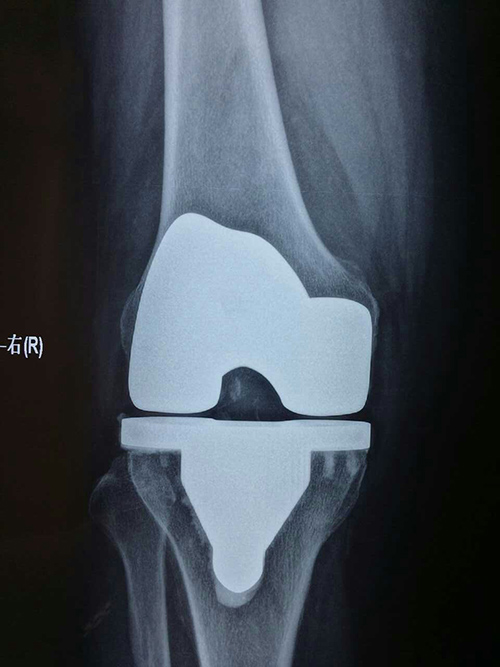

屈膝120°

伸膝0°

他告诉李主任,现在的他每天早晚可以进行两次常规的散步,路程大约4华里。汪老伸膝可达到0度,屈膝达到120度,上下楼梯正常,并且可以慢跑了!看着汪老完美的术后表现,李主任深感欣慰,他告诉我们,汪老人很热情,临走时还问他要了一些名片,说有类似病情的朋友一定要他们来找他咨询就诊。李主任说,看到自己手术的成功能够让一个又一个患者远离病痛的折磨,是他从医二十多年来一直的理想与坚持,做一名外科医生是自己最不后悔的选择,而做一名好的外科医生更是自己一生的追求!当看到患者顺利治愈康复出院时,也就是他觉得最自豪、最欣慰的时刻。